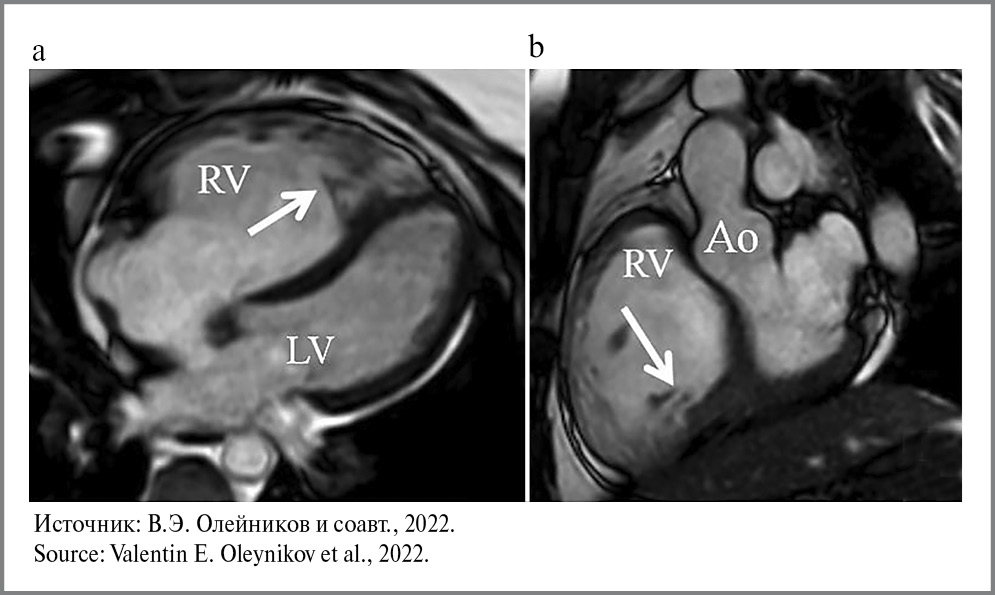

Наиболее характерными считаются изменения в базальных отделах и в задней стенке ПЖ [34, 42]. Однако ЭхоКГ не всегда позволяет дать адекватную количественную оценку глобальных размеров и функции ПЖ. МРТ позволяет визуализировать в миокарде жировые отложения, а при контрастировании – фиброзные изменения (рис. 3) [39, 44], поэтому МРТ сердца представляется наиболее оптимальным методом визуализации при АДПЖ [42].

Рис. 3. МРТ при АДПЖ: а – участки жировой инфильтрации при нативном сканировании; b – фиброзные изменения при постконтрастном исследовании; c – повышенная трабекулярность ПЖ. / Fig. 3. MRI for arrhythmogenic right ventricular dysplasia: a – areas of fatty infiltration in native scanning; b – fibrotic changes in post-contrast examination; c – increased trabecularity of the right ventricle.